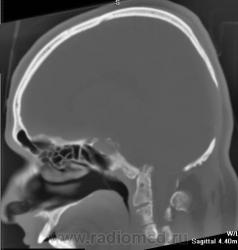

Nela. КТ головного мозга и костей. Гистиоцитоз Х (морфологическая верификация).

Пациент - молодой человек, предъявляет жалобы на головные боли и боли в шее. Болеет с 2002 года.

Гистиоцитоз Х – заболевание ретикулоцитарной системы неизвестной этиологии, морфологически характеризующееся первичной пролиферацией своеобразных гистиоцитов (клеток Лангерганса или клеток Х) и образованием в легких и в других органах и тканях гистиоцитарных гранулем и гранулематозных инфильтратов.

Заболевание относится к системным: гранулемы могут образовываться в различных органах, но наиболее часто поражаются легкие и кости. Заболевают чаще всего люди молодого возраста, между 20 и 40 годами, большей частьюмужчины.

Легкие наверняка исследовались, так как больной долгое время обследовался и лечился не только у нас, но и в центральных институтах. Я лично снимков легких не видела. Никаких указаний на поражение легких не было.